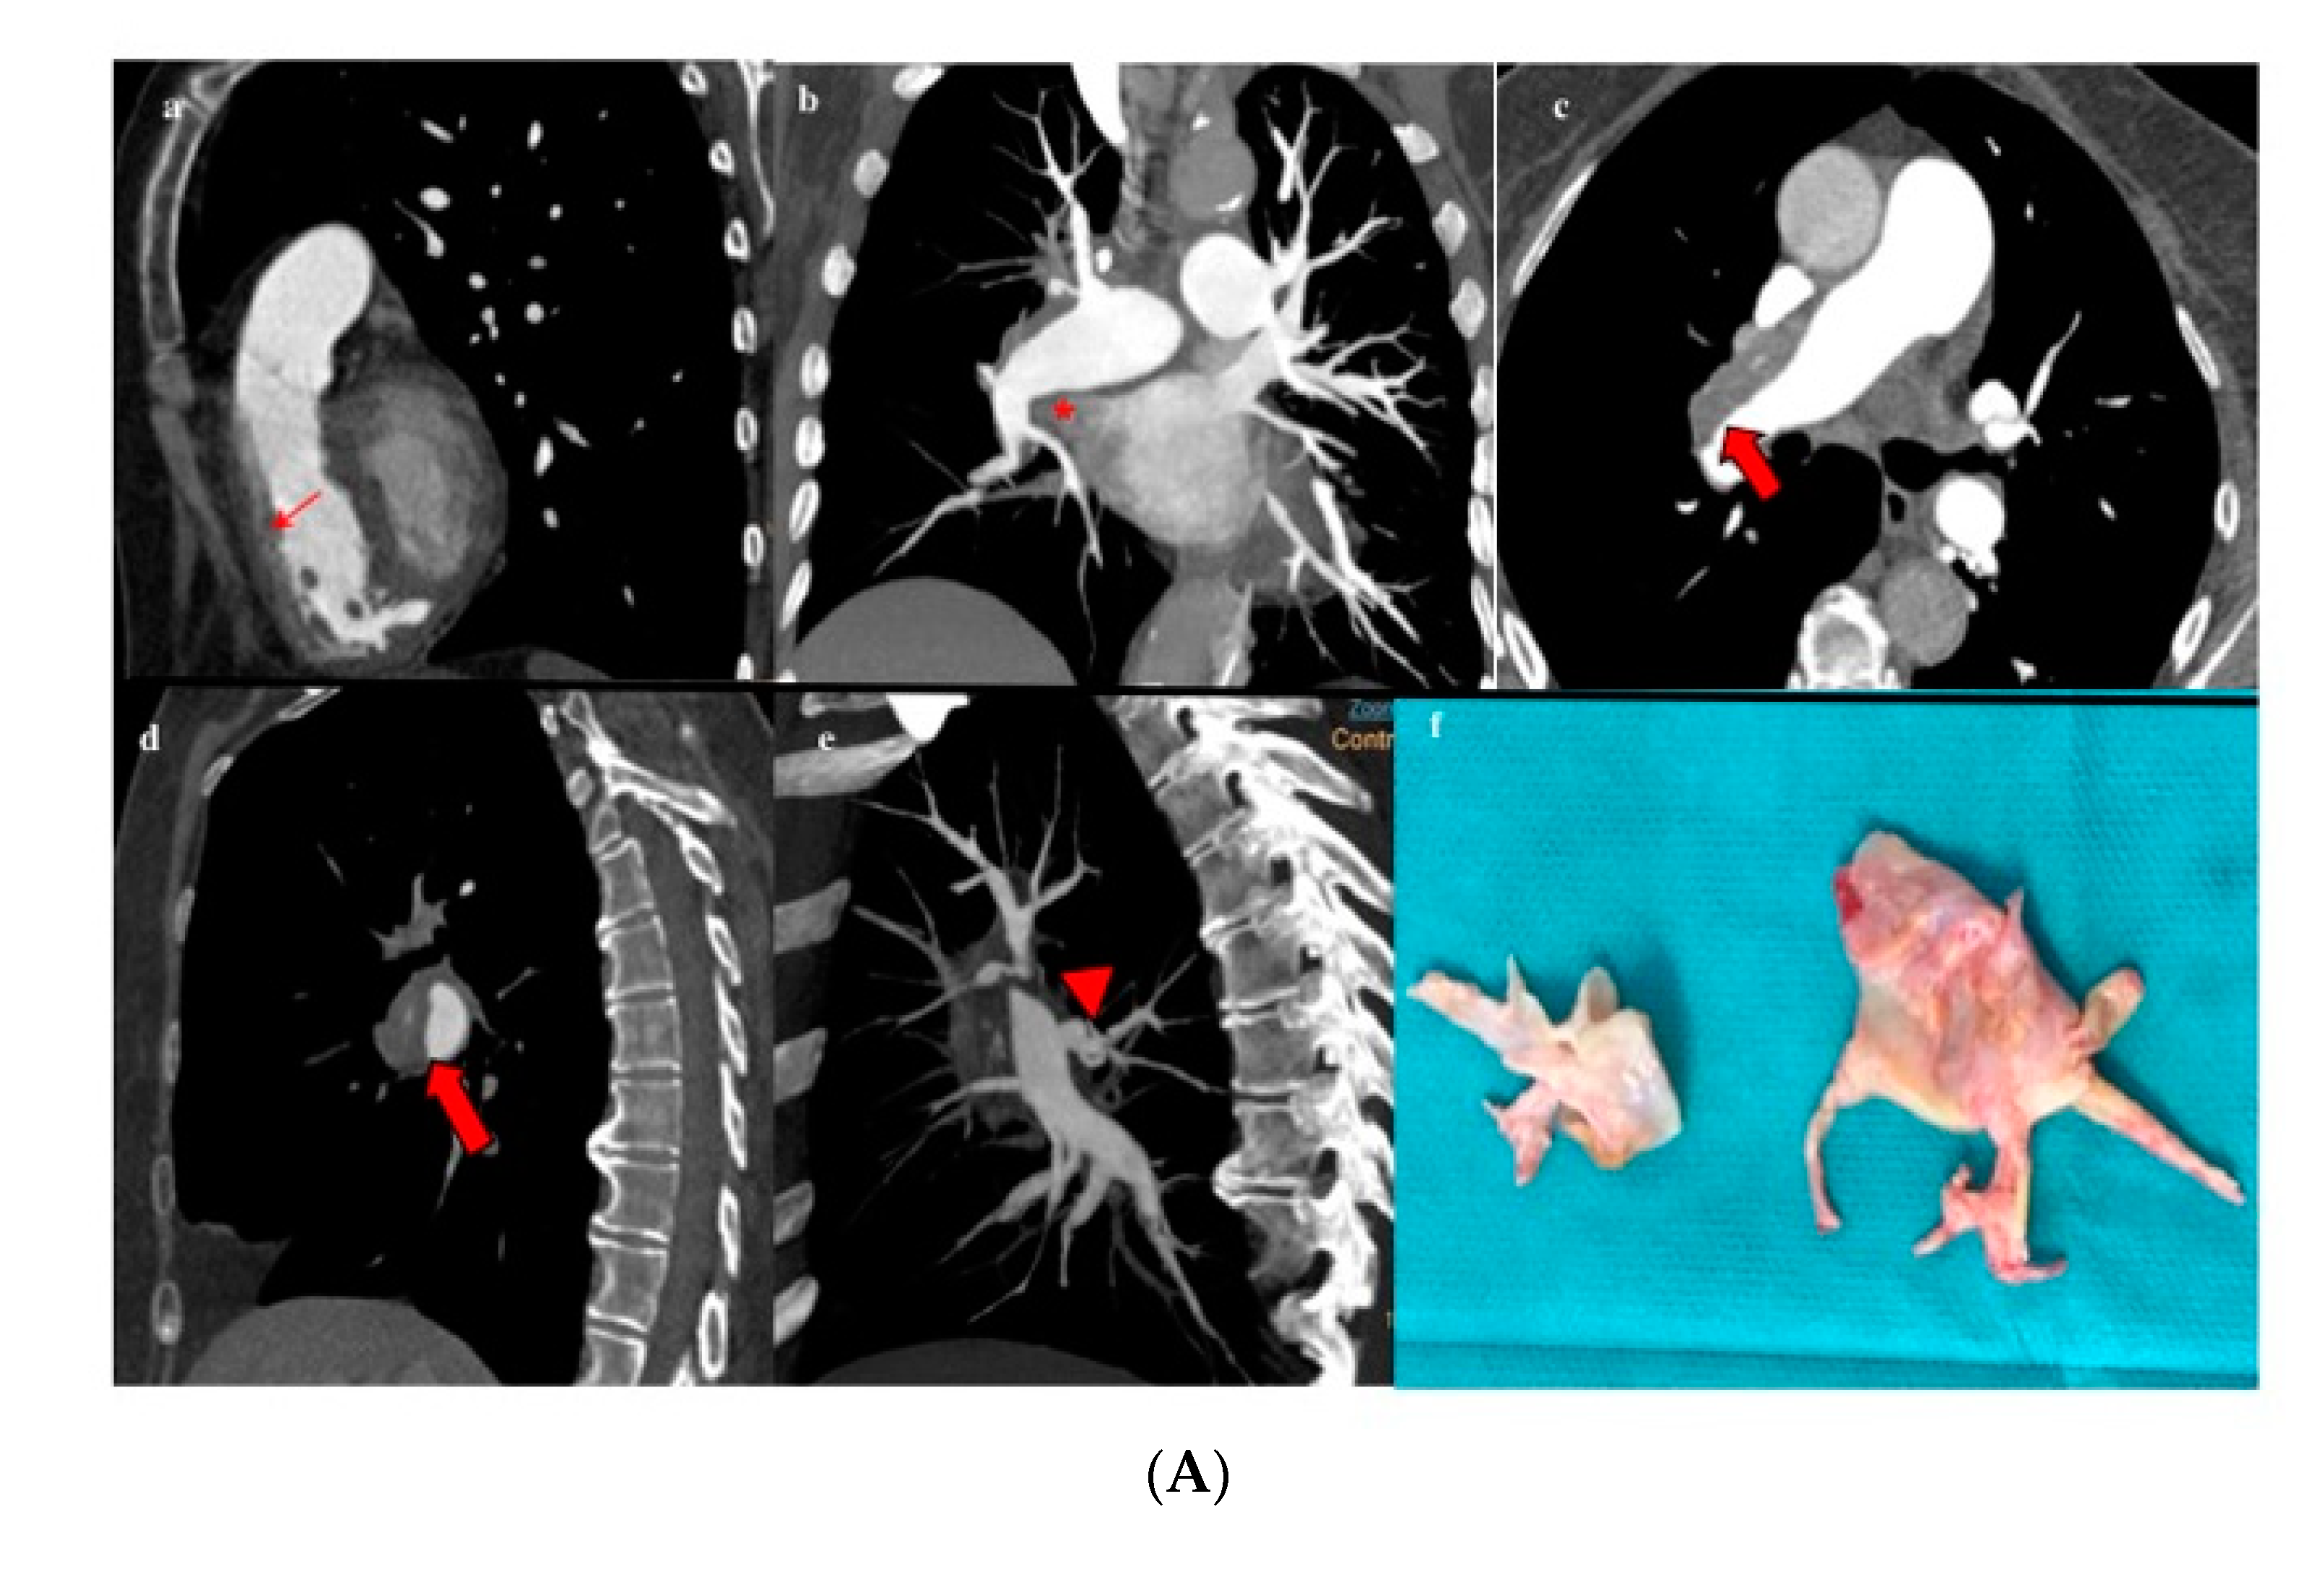

Figure 5.

Patient with proximal CTEPH (A). (a,b) Rectified interventricular septum (red thin arrow) and reduction of venous return (*). (c–e) Thromboembolic disease affecting the main pulmonary artery (red thick arrow) with extension to the right upper lobar artery (arrowhead). (f) Surgical specimen showing level I disease. Patient with distal CTEPH (B). (a–f) Organized intravascular material (thin red arrows) is identified at distal-segmental/subsegmental levels in all the pulmonary lobes. (g) Surgical specimen showing level III disease.

Amidst those patients who underwent PEA (n = 91), 18.7% had level I disease (Figure 5A), 45.1% level II disease, and 36.3% level III disease (Figure 5B). Table 1 summarizes the proportion of intervened patients for whom the surgical decision was based on MCTA compared with those who needed a complementary PA regarding intraoperative CTEPH classification. In up to 54% of intervened patients with level III disease, a decision on operability had been made exclusively on MCTA.